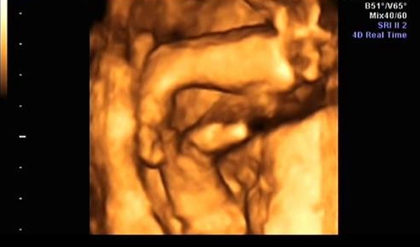

网上有一种说法是,在做四维彩超的时候,如果是女宝宝是比较不容易配合的,如果是男宝宝更容易通过,那么是不是四维女宝更容易配合呢,四维女宝特征有哪些?更多关于生男生女的相关内容尽在孕宝网。

四维女宝宝特征有哪些?